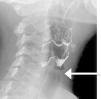

La ecografía tiroidea mostraba 3 colecciones hipoecogénicas próximas sugestivas de absceso tiroideo. Mediante PAAF se obtuvo material purulento en cuyo cultivo se identificó Lactococcus lactis sensible a penicilina. Los hemocultivos fueron negativos. Mediante esofagograma baritado se evidenció fístula del seno piriforme izquierdo que terminaba en la proximidad de la glándula tiroidea (fig. 1) y que se confirmó posteriormente en tomografía cervical.

La ecografía tiroidea permite visualizar el absceso tiroideo, revelando una lesión heterogénea e hipoecoica. En cuanto al diagnóstico de la FSP, la laringoscopia es considerada por algunos autores como la técnica de imagen de elección1, sin embargo, otros autores apuestan por el esofagograma con bario o la TAC «under trumpet maneuver», es decir, con el empleo de aire como medio de contraste, como la mejores técnicas7. Existe un mayor rendimiento de la técnica cuando se realiza al menos 15 días tras la resolución del cuadro agudo, debido a que la presencia del absceso puede obliterar el trayecto fistuloso y ocasionar un resultado falso negativo4. La búsqueda activa de una FSP es obligatoria en niños con TAS de repetición, y recomendable en el resto de casos.